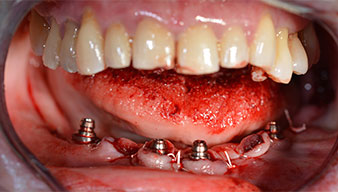

After removal of the residual dentition in the mandible, the alveolar crest was exposed from 37 to 47.

The mental foramen was first identified as a limiting anatomical structure and then the cortical bone of the crest was smoothed with the straight handpiece and a large rose-head bur (Fig. 4).

The impression and bite registration were then performed so that the dental technician could begin producing the provisional restoration immediately. This was then screwed in on the same day (Fig. 17 and 18).

Implants

Fig. 17

Fig. 18